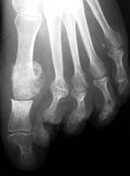

Es una deformidad de los dedos del pie que altera el funcionamiento normal del pie y puede producir dolor por el roce entre el dedo y el calzado.

Existen una serie de factores predisponentes pero el factor principal es la alteración de la musculatura intrínseca del pie. En ocasiones, la deformidad del dedo se acompaña de alteraciones en la articulación metatarsofalángica.